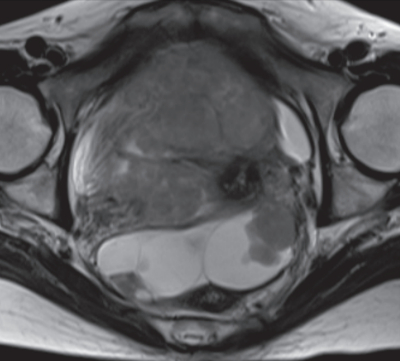

血液所見:赤血球 370 万、Hb 10.8 g/dL、Ht 32 %、白血球 8,800、血小板 19 万。血液生化学所見: 総蛋白 6.8 g/dL、アルブミン3.3 g/dL、総ビリルビン 0.9 mg/dL、AST 28 U/L、ALT 40 U/L、尿素窒素 20 mg/dL、クレアチニン 0.8 mg/dL、CEA 2.8 ng/mL(基準 5 以下)、CA19-9 30 U/mL(基準 37 以下)、CA125 1,280 U/mL(基準 35 以下)。CRP 1.0 mg/dL。骨盤部 MRI T2 強調水平断像、矢状断像及び腹部造影 CTを別に示す。審査腹腔鏡(腹腔鏡下試験切除術)で、腫瘍の播種病変との癒着により骨盤内臓器の同定はできず、腫瘍生検のみ施行した。病理診断の結果は高異型度漿液性癌であった。